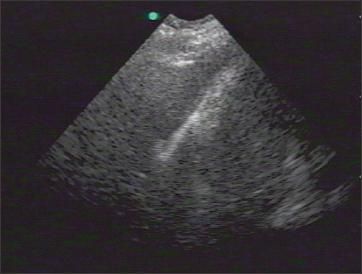

Static signs, such as the comet tail artifact, or the observation of consolidated lung parenchyma or lung tissue that contains a solid mass also can be useful in excluding pneumothorax (Figure 5).11 The presence of lung sliding or comet tails is highly sensitive for the absence of anterior pneumothorax in the supine patient. However, if these signs are not present, confirmation by either a chest radiograph or a CT scan is recommended.

Figure 5 –

The comet tail artifact (arrow) is an example of a static sign that can be useful in excluding pneumothorax.